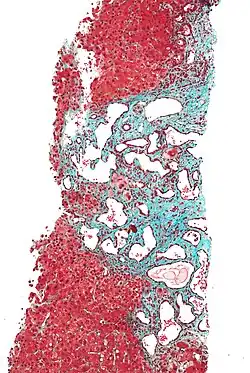

Low magnification micrograph of a bile duct hamartoma. Trichrome stain.

Low magnification micrograph of a bile duct hamartoma. Trichrome stain. -